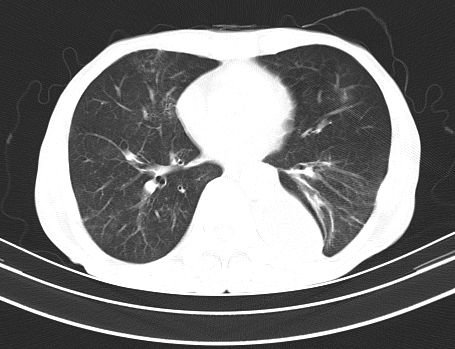

以下是引用gaoshengjiang在2008-5-30 19:53:00的发言:[br]右上叶可见大片实变影,其内可见充气支气管影及囊状影,右上叶尖端支气管走形区可见结节样影,左侧胸腔内可见胸腔胃影。纵隔淋巴结肿大。[br]考虑:1.右上肺阻塞性肺炎伴肺脓肿形成。支持转移所致。[br] 2.左侧胸腔胃。